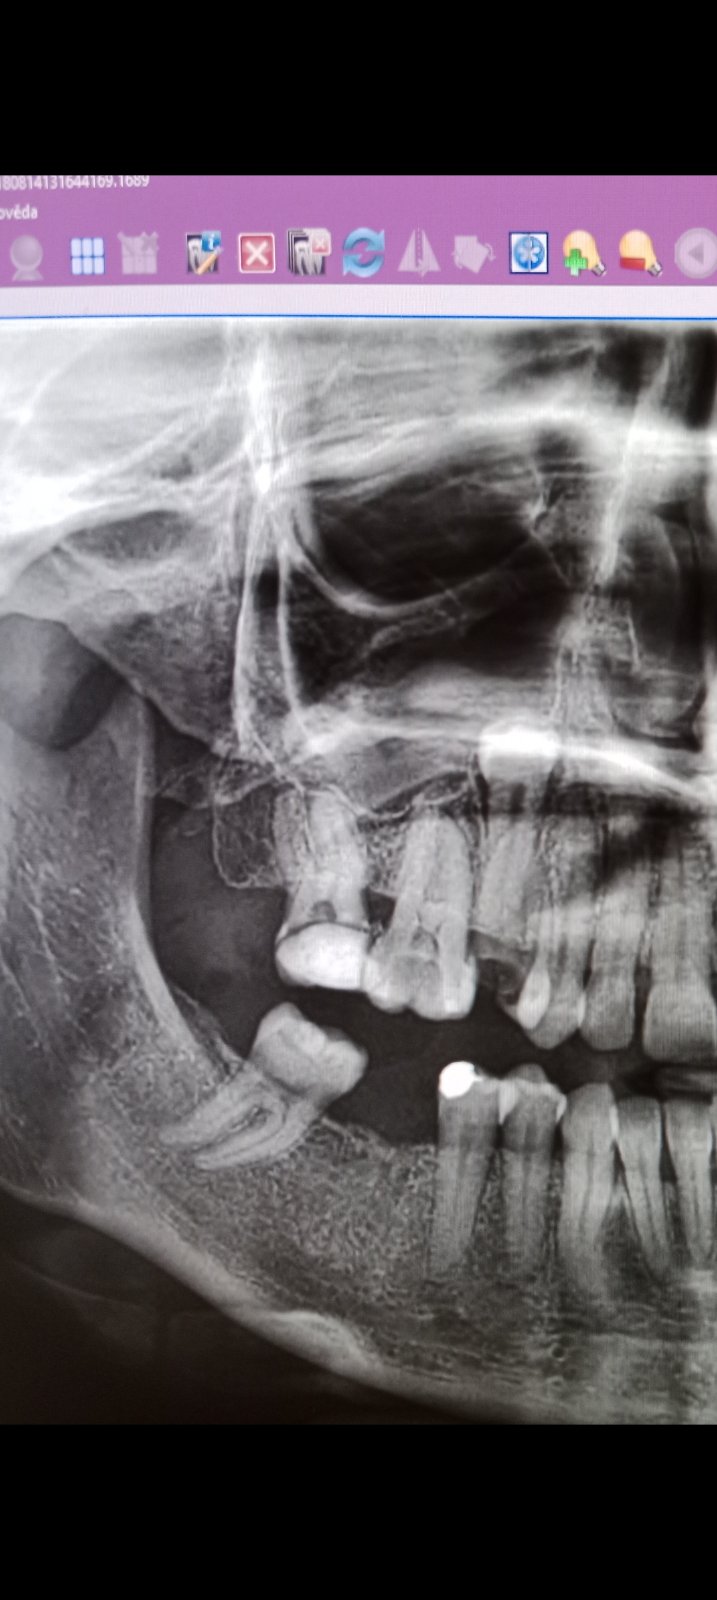

Pekný deň idú mi ťahať horný Zub ktorý vyrástol opačne